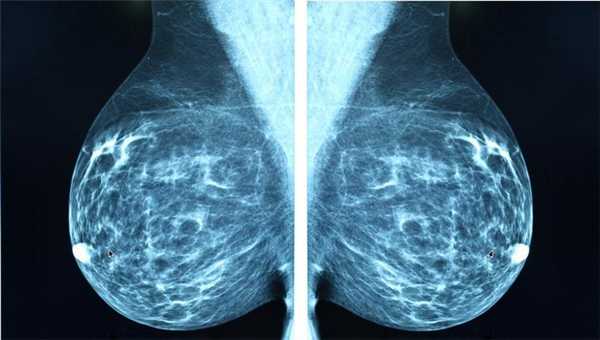

Маммография

Отдельный вид рентгенографии, разработанный для диагностики заболеваний молочной железы, поэтому проходят маммографию женщины. О рекомендуемом возрасте для проведения процедуры единого мнения нет. Маммография помогает убедиться в отсутствии злокачественной опухоли с точностью до 89%. Считается, что женщины должны проходить обследования регулярно, начиная с 39 лет, хотя некоторые онкологические сообщества рекомендуют обследоваться с более молодого возраста.

Маммографию назначают для диагностики рака молочной железы, процедура проходит быстро, это плюс, но пациентку облучают, а риск неверного диагноза остаётся, это минус. Маммография может быть цифровой и плёночной, цифровая маммография обеспечивает получение более чёткого снимка.